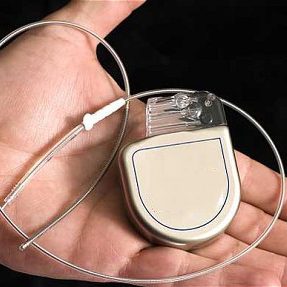

Cardioverter